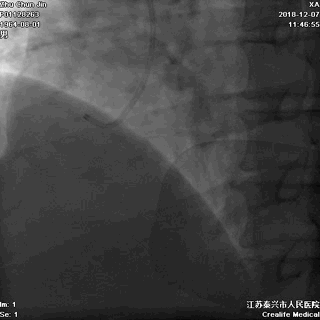

胸部透视,看看心影吧:

▲胸部透视见纵隔影似乎明显增宽!是夹层吗?

接下来是经猪尾导管行主动脉造影,还是行其它检查呢?